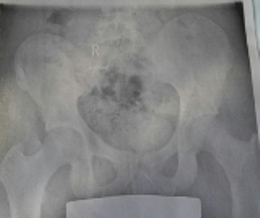

- Rechtskonvexe Thorakolumbale Skoliose von 28 Grad (Bild im Anhang)

- Beckenschiefstand (Bild im Anhang)

Ansicht von vorne

20151219_150853.jpg (26.85 KiB) 10493 mal betrachtet

20151219_150925-1.jpg (28 KiB) 10493 mal betrachtet

Es wurde ein Beckenschiefstand von 1,6cm gemessen.

Hauptkrümmung: Thorakolumbal rechtskonvex 28 Grad Rotation: II

Gegenkrümmung: Thorakal links 28 Grad Rotation: I

Gegenkrümmung: Lumbal links 13 Grad Rotation: I